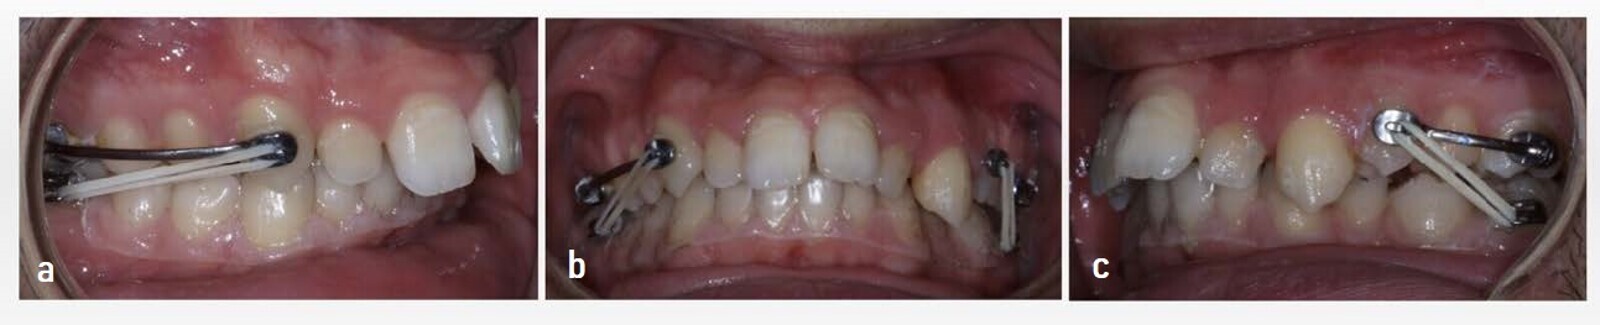

Upon intra-oral examination, all the permanent teeth were visible, except for the mandibular third molars. The molar relationship was a complete Class II, in both arches, and the canine relationship was also Class II, for both the right and left sides. There was mild crowding in both arches, tooth #34 being in linguoversion. The overbite covered more than two-thirds of the surface of the mandibular incisors. A most notable feature was an excessive overjet of approximately 11 mm (Fig. 2).

Figs. 2a–e: Initial intra-oral photographs.